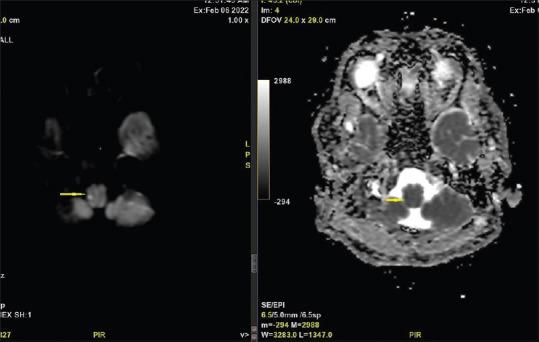

Lateral medullary syndrome (LMS) or Wallenberg's syndrome is an uncommon and often underdiagnosed cause of posterior circulation stroke. Thrombosis, embolization, or dissection of vertebral or posterior inferior cerebellar artery (PICA) often results into LMS. The most pathognomonic symptoms of LMS includes pain and temperature deficits on ipsilateral facial side and contralateral side of rest of the body, ipsilateral ataxia, vertigo, nystagmus, dysphagia, hoarseness, hiccups and Horner's syndrome. We report a case of LMS in a 49-year-old Indian female with no known classical risk factors for stroke who presented with chief complaints of debilitating headache. Clinical examination was suggestive of LMS and radiological investigation confirmed the diagnosis. Patient's hospital stay was uneventful and she was discharged to home with gradual improvement in her symptoms.